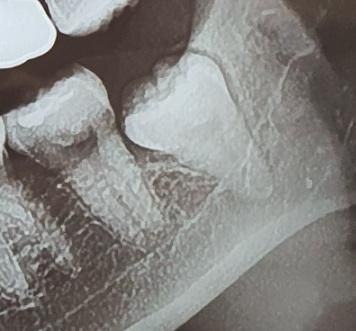

• 1번 째 사진

사진으로 보이는 사랑니는 잇몸 안에 완전히 맹출되어 있고 주변 조직에 특별한 문제를 일으키지 않습니다. 따라서 통증을 유발할 가능성은 매우 낮습니다.

해당 부위에 다른 통증의 원인이 있지 않은지 확인해보는 것이 좋습니다. 매우 깊게 매복되어 있는 사랑니기 때문에 일반 병원에서는 발치를 해주지 않을 경우도 있습니다. 이런 경우에는 대학 병원에 구강 외과에서 발치를 하는 것이 좋을 수 있습니다.

저정도 깊이라면 일단 CT를 찍어보셔야될것같습니다. 엑스레이 상으로는 신경관과는 닿아 잇진 않고 신경관 옆으로 치아가 위치한거 같습니다.

위 사진만으로는 명확히 알 수는 없으나 신경이 가까운 부위는 맞기에 대학병원 가시는 게 좋습니다.

뼈 속 깊이 박혀있고, 신경관과도 가까워서 아마 개인치과에서는 대학치과병원이나 사랑니 전문병원 가라 할 것 같습니다. 물론 자신있는 원장은 자기가 뽑아주겠다 할거고요